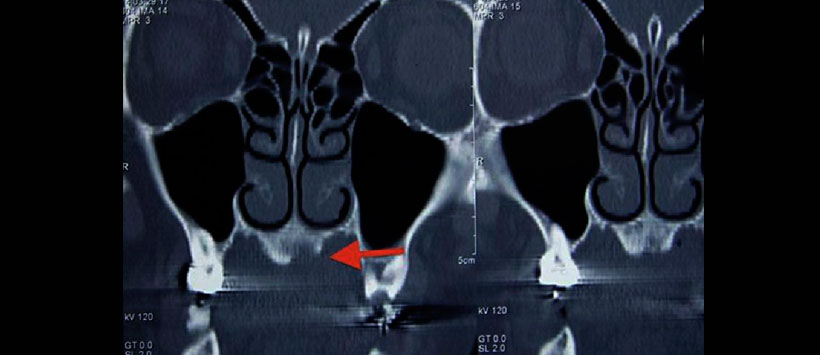

Figura 2: Tomografía computarizada (Vista axial). Prominencia de exostosis (torus) en el paladar duro)

Figura 3: Tomografía computarizada (vista lateral). Torus palatino con discontinuidad de la cortical, se aprecia zona de erosión ósea